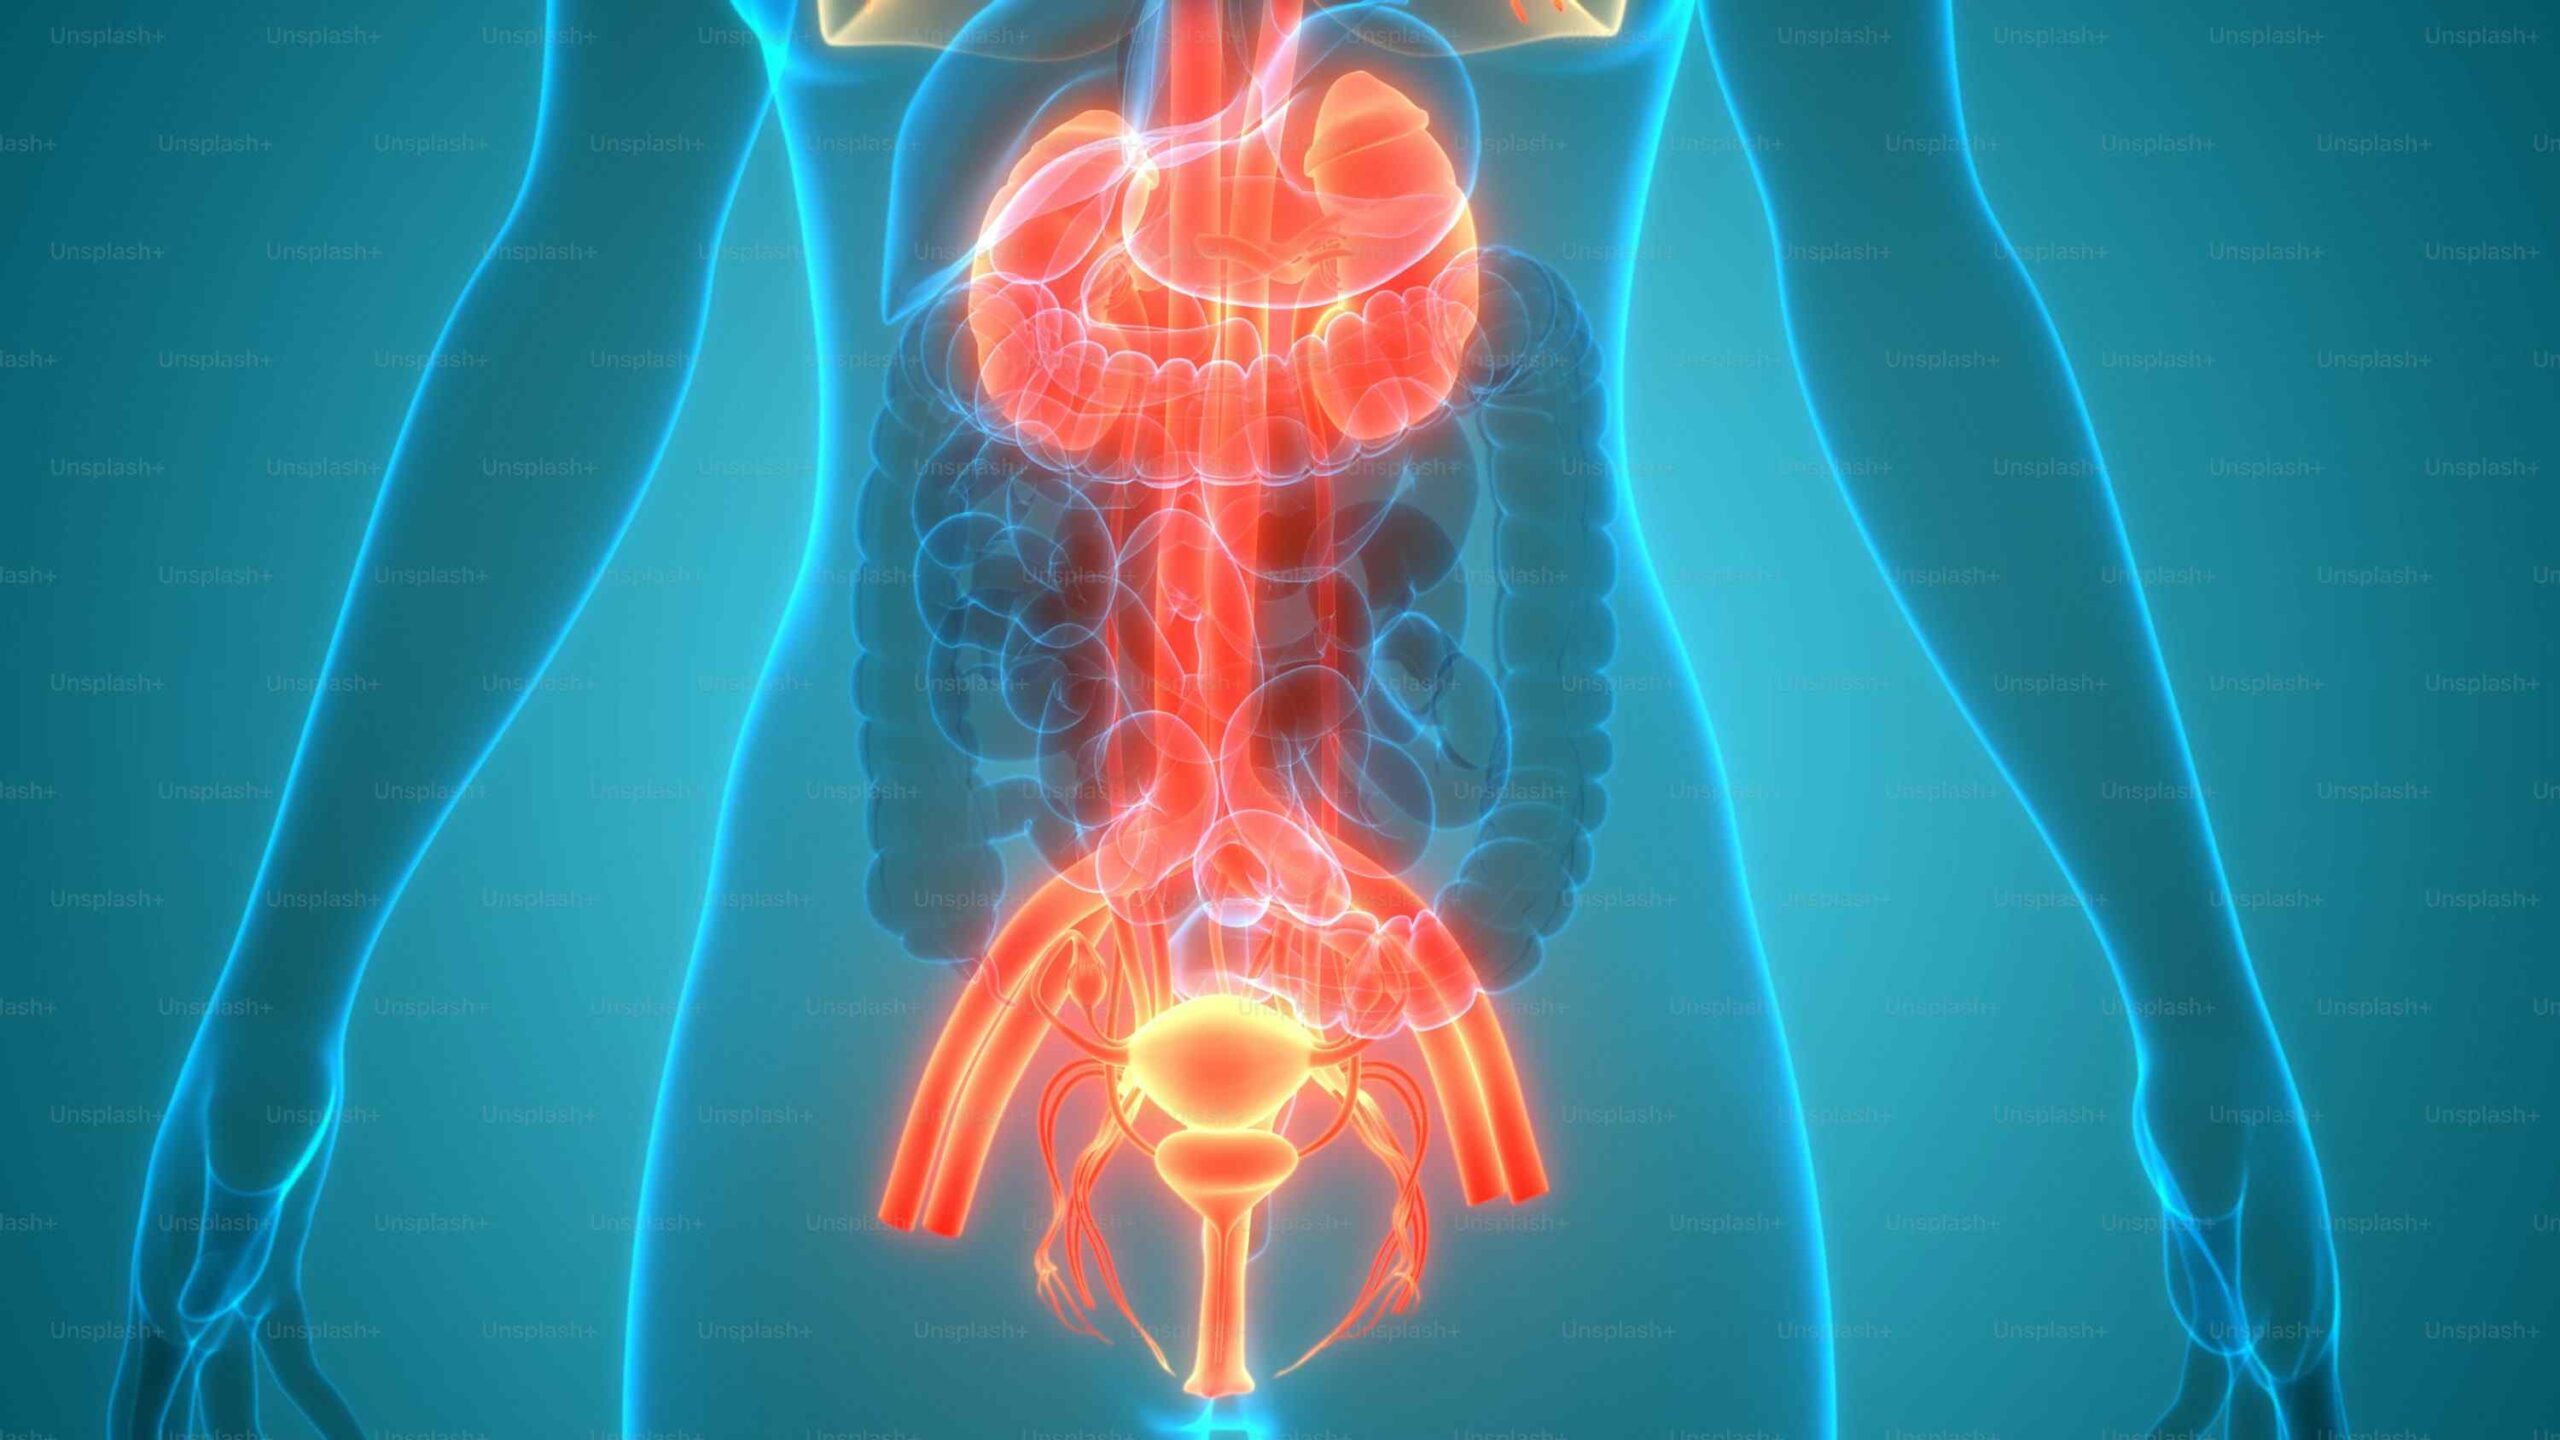

Your gut is not just for digestion — it influences immunity, mood, skin, weight, and even hormones. Poor gut health can show up as bloating, acidity, constipation, loose stools, fatigue, brain fog, or frequent illness. Processed food, antibiotics, stress, and lack of sleep can disturb the gut microbiome.

To support gut health, include fiber-rich vegetables and fruits, fermented foods, enough water, and regular meals. Avoid constant snacking, excessive sugar, and late-night eating. Chewing food well and eating mindfully also make a big difference. A healthy gut improves nutrient absorption, reduces inflammation, and supports overall wellness. Healing the gut is often the first step in managing issues like PCOS, obesity, and fatty liver.